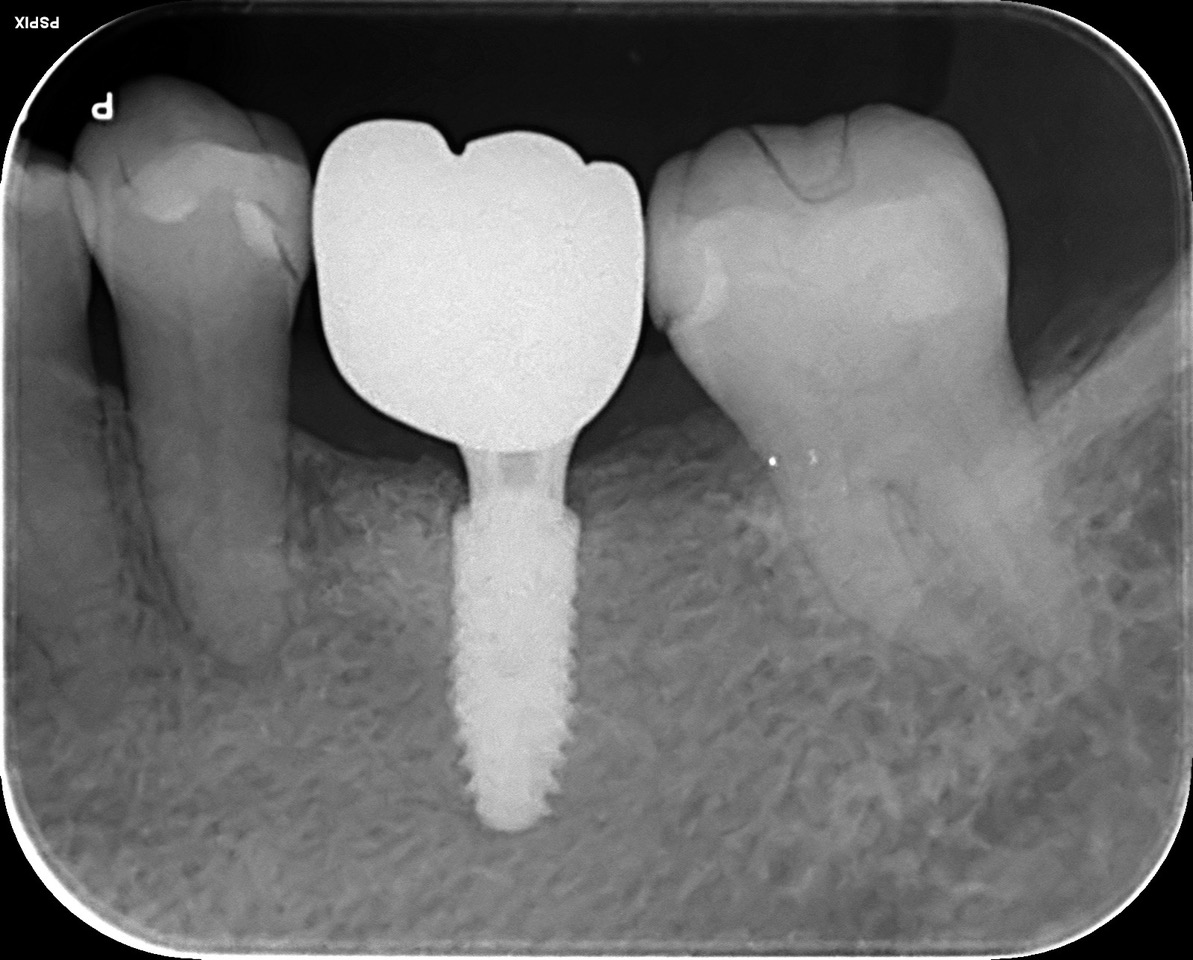

CASE 01

| 主訴 | 歯が割れた |

| 治療内容 | 左下6番 インプラント治療(骨の再生療法含む) |

| 治療回数 | 14回 |

| 治療費用 | ¥460,000 |

| 想定される副作用 | 腫れ、痛み |